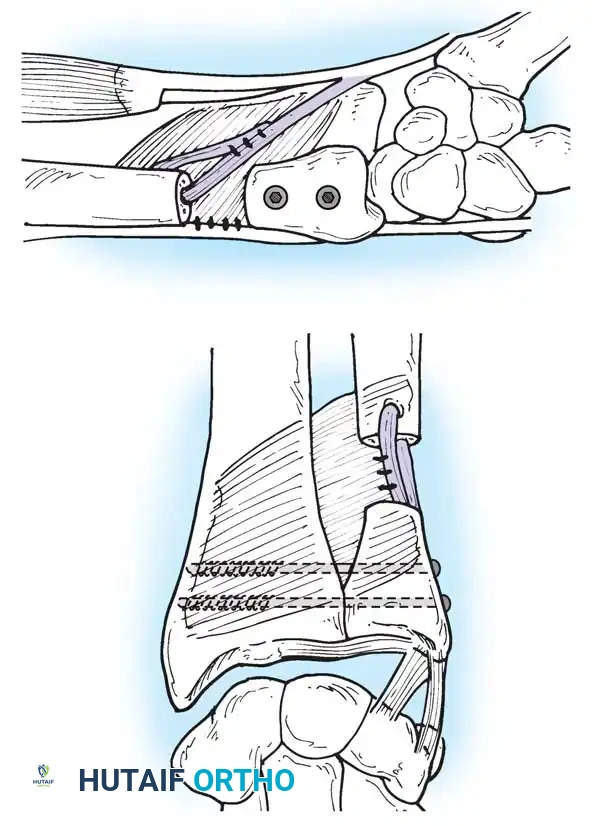

Preparation of the distal ulna: Drill holes are created at the fovea to facilitate transosseous suture passage for anatomic TFCC reattachment.

Transosseous Repair Technique:

1. Identify the foveal detachment arthroscopically or via an open dorsal ulnar approach.

2. Prepare the ulnar fovea down to bleeding bone using a burr or curette to stimulate a healing response.

3. Utilize a targeting guide to drill two converging osseous tunnels from the ulnar neck into the fovea.

Passing non-absorbable sutures through the osseous tunnels in the ulna to capture the peripheral edge of the TFCC.

- Pass strong, non-absorbable sutures (e.g., 2-0 FiberWire) through the TFCC using an outside-in or inside-out technique, then shuttle the suture limbs down the osseous tunnels.

The sutures are tied securely over the cortical bone bridge of the ulnar neck, restoring tension to the radioulnar ligaments.

- Tie the sutures over the ulnar cortical bridge with the forearm in neutral rotation to restore anatomic tension.